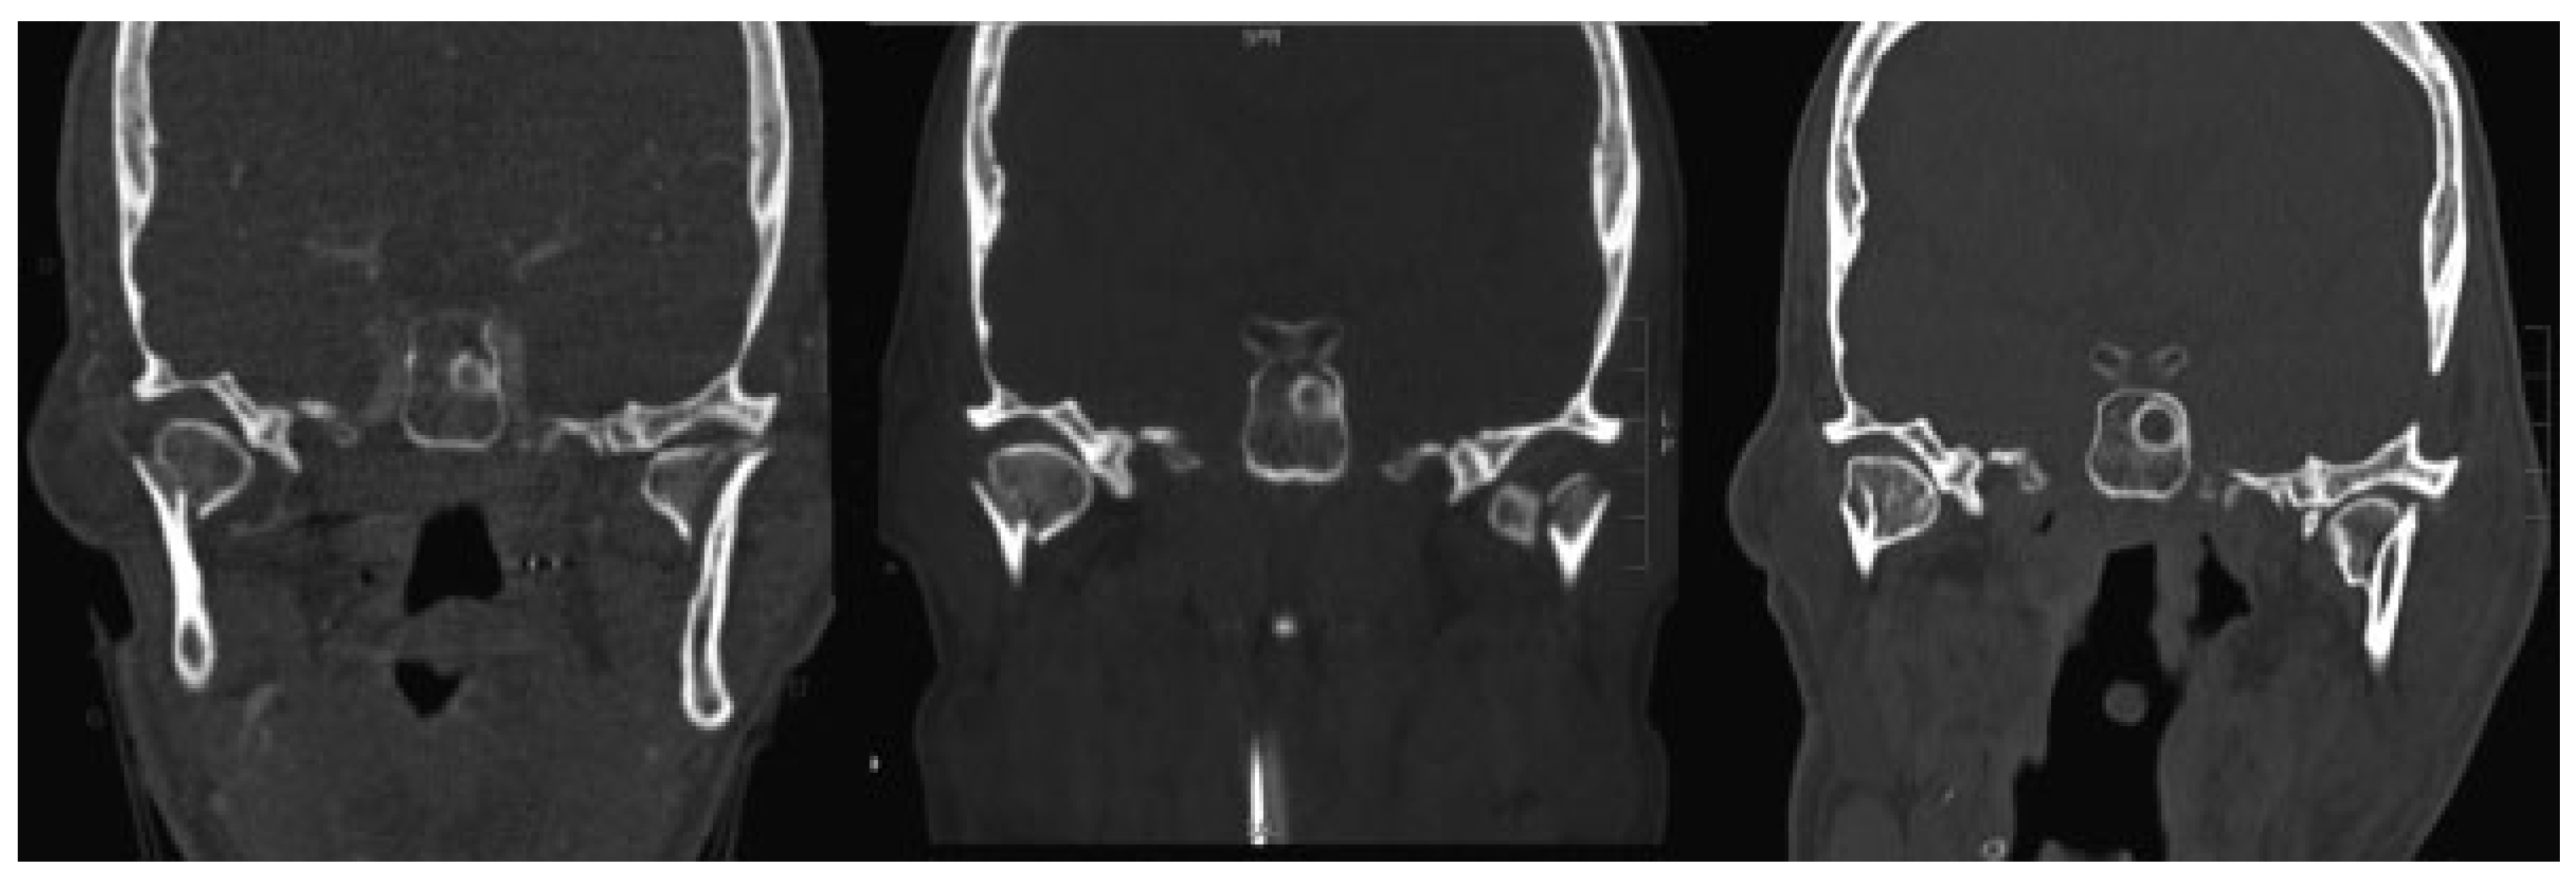

Predictor variables: Predictor variables were factors potentially associated with complication rates and were classified as demographic, injury-related, and treatment variables. Demographic factors included age (years), sex (male or female), and race (Caucasian, black, or other). Injury-related variables included mechanism, admission Glasgow coma scale (GCS), length of hospital stay, and injury severity score.[22] Anatomic level of condylar fracture was defined according to Lindahl’s classification.[23] Bilateral con- dylar fractures were classified into three types according to Chen’s classification system, with type I defined as bilateral condylar head (intracapsular) fractures, type II as one condylar and one subcondylar fracture, and type III as bilateral subcondylar fractures (Figure 1).[15] In addition to condylar fracture characteristics, facial fracture patterns including the presence of noncondylar mandible fractures, concomitant midface fractures, and midface and mandibular fractures that required operative intervention were considered as well. The facial injury severity score (FISS) was calculated to account for the overall severity of facial trauma.[24]

Figure 1. Chen’s classification system of bilateral mandibular condylar fractures based on the level of injury. Type I: bilateral intracapsular condylar fractures (left); type II: one condylar and one subcondylar fractures (middle); type III: bilateral subcondylar fractures (right).